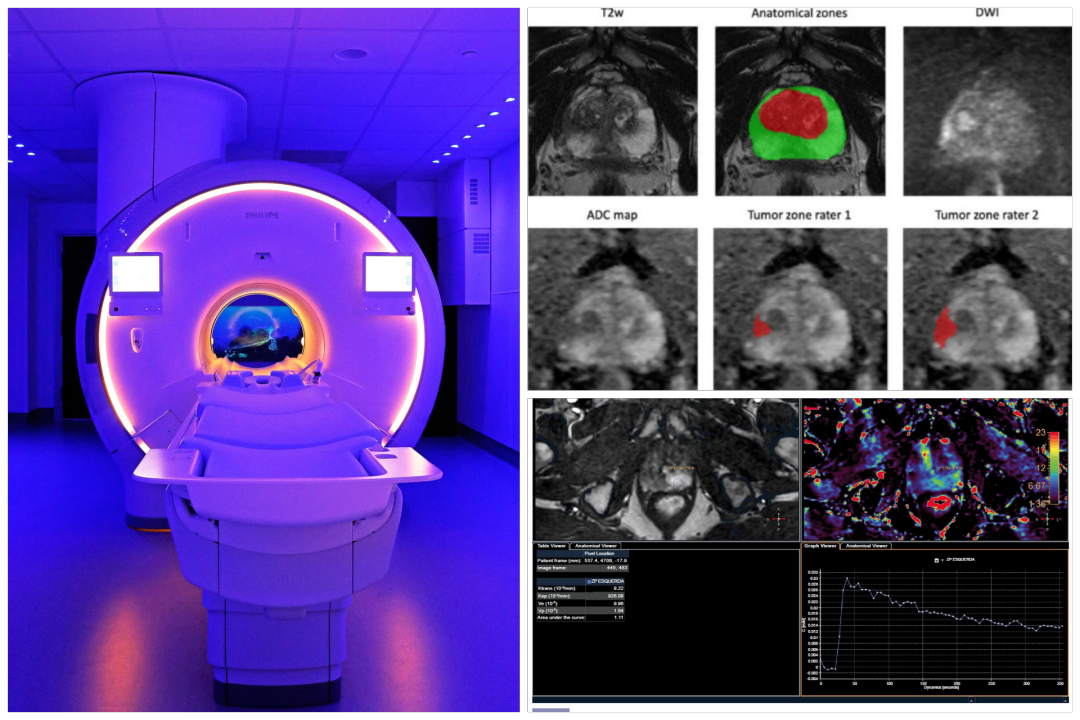

Πραγματοποιείται σε εξειδικευμένα κέντρα με μαγνητικούς τομογράφους 3 Tesla για εικόνες υψηλής ευκρίνειας.